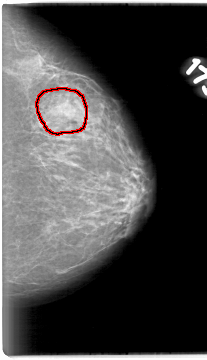

D_4016_1.LEFT_MLO

LEFT_MLO LINES 5386 PIXELS_PER_LINE 3241 BITS_PER_PIXEL 12 RESOLUTION 43.5 OVERLAY

FILE: D_4016_1.LEFT_MLO.OVERLAY

TOTAL_ABNORMALITIES 1

ABNORMALITY 1

LESION_TYPE MASS SHAPE IRREGULAR MARGINS ILL_DEFINED

ASSESSMENT 0

SUBTLETY 5

PATHOLOGY BENIGN

TOTAL_OUTLINES 1

BOUNDARY